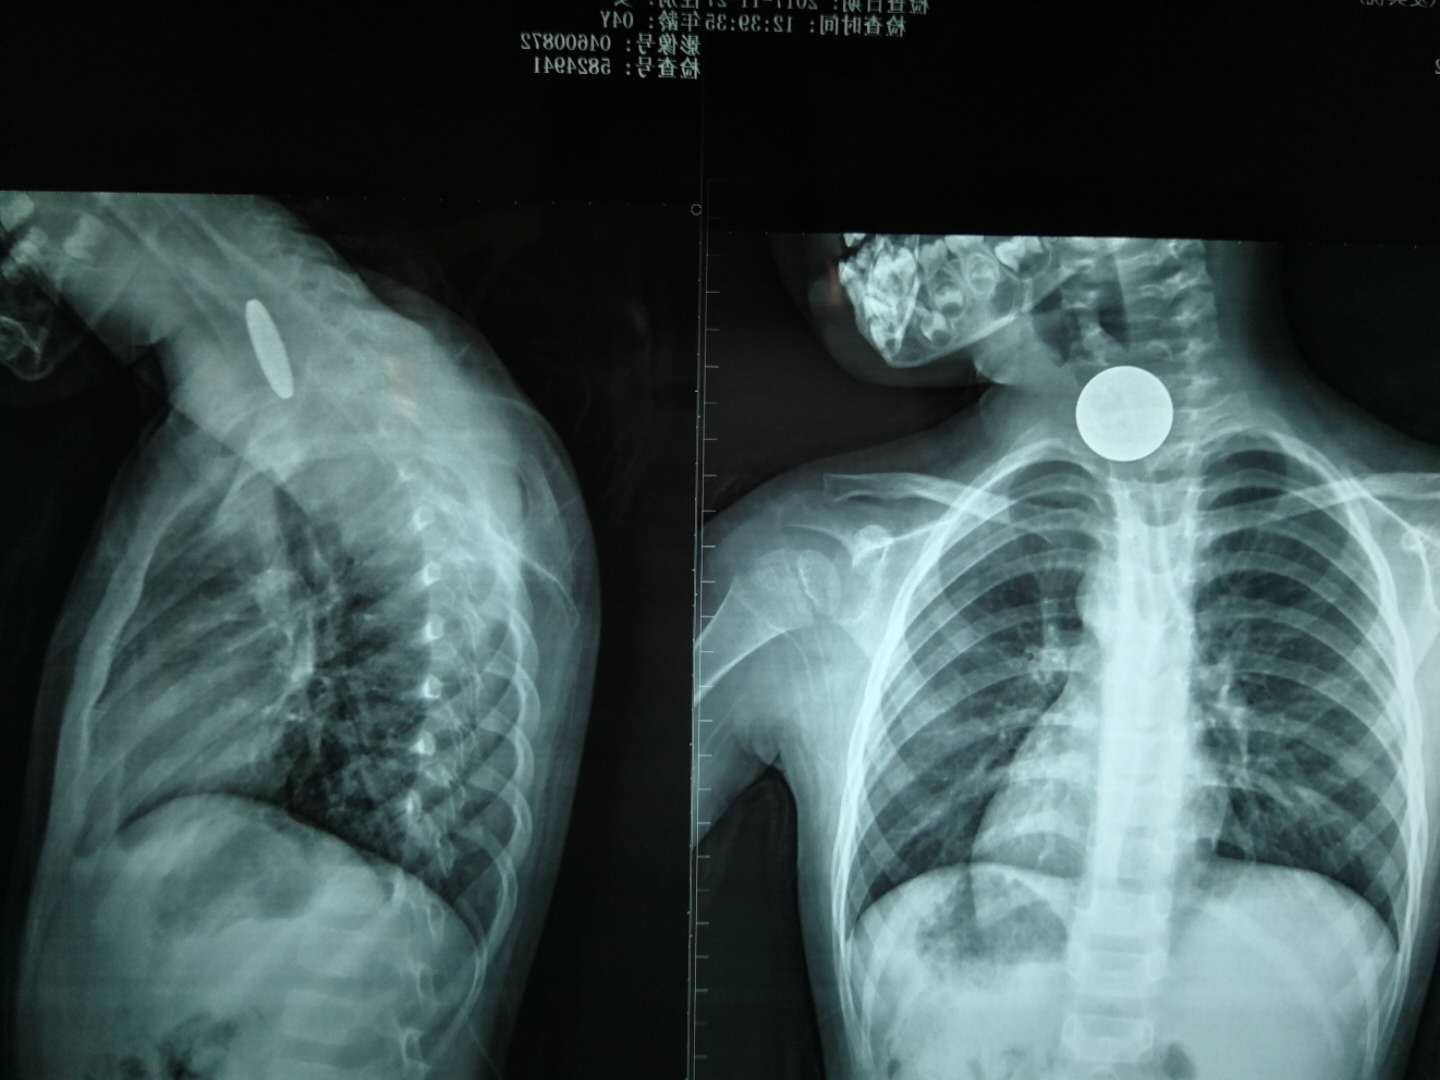

“醫(yī)生,快看看我的孩子!”這么焦急的聲音,到底發(fā)生了什么事?原來,11月27日上午11點(diǎn),一個(gè)4歲的女孩獨(dú)自玩耍時(shí)不小心吞下了一枚1元硬幣,家長發(fā)現(xiàn)后立即將小孩送到我院急診科就診。在為女孩做了頸部和胸部的X光片檢查后,醫(yī)生發(fā)現(xiàn)硬幣卡在女孩的食道中間的狹窄段(注:非進(jìn)食狀態(tài)下食道呈閉合狀)。